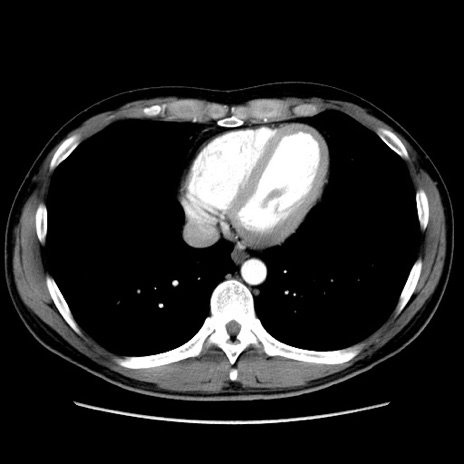

冠状断像

症例36(横断像)

【症例】20歳代 男性

【主訴】心窩部痛

【現病歴】今朝より上腹部痛あり。一旦軽快していたが再度出現したため救急要請。昨日夕に白身の魚を含む刺身を食べた。

【身体所見】BP 136/89mmHg、HR 74/min、BT 37.0℃、腹部:膨満、軟、心窩部に圧痛あり。反跳痛なし、筋性防御なし、腸雑音やや亢進あり。

【データ】WBC 17700、CRP 0.48